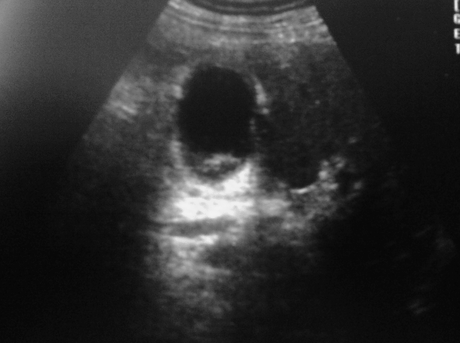

Еще так

Да, все верно. Только в просвете еще и конкременты (может снимок не совсем удачный, больше хотелось вывести "дырку" в стенке, а не камень, но он был

Кстати нарушение целостности видно и здесь: Послеоперационный диагноз (списала с истории болезни): ЖКБ.Острый калькулезный гангренозный холецистит. Перфорация желчного пузыря. Местный перитонит.